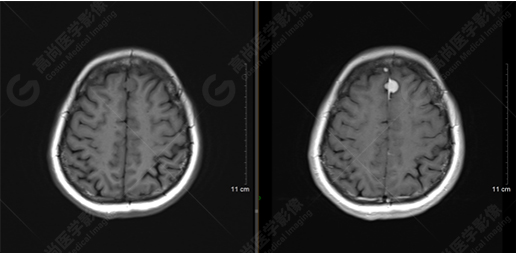

以上是常規(guī)顱腦MRI對(duì)病灶作出的診斷,可以看出,患者橋腦及大腦鐮各有一病灶,那么兩個(gè)病灶是否對(duì)顱腦神經(jīng)纖維束走行都有影像呢,下面是橋腦病變附近的神經(jīng)纖維束成像——皮質(zhì)脊髓束:

DTI成像示皮質(zhì)脊髓束橋腦段受壓向外側(cè)移位。圖像能清楚的顯示神經(jīng)纖維束與病灶的關(guān)系,是一種推壓移位的表現(xiàn)。